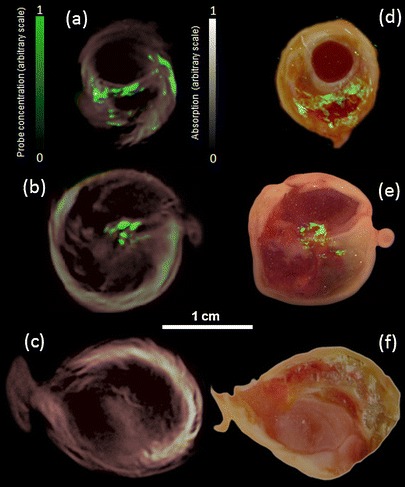

Three-Dimensional Visualization of MMP Activity from an Intact Specimen with MSOT

In order to resolve MMP activity with high-resolution over non-specific intrinsic tissue background and inactive probe accumulation, we performed the MSOT imaging, as previously described in the phantom section. The results in Fig. 4 are shown for three representative specimen, two MMPSense-incubated and one control plaque. Panels a, b and c show cross-sectional MSOT reconstructions, clearly revealing an intra-plaque area with increased signal referred to as ‘hot spots’ (shown in green), superimposed onto morphological optoacoustic images (made using single 635-nm wavelength). The hot spots are characterized by increased MMP activity as the spectrally resolved MSOT signal originates only from the activated MMPSense™ 680. For validation, epi-fluorescence images of dissected plaque (50-μm sections), superimposed on the corresponding color photographs (panels d, e and f), were done at approximately the same level and match well the corresponding MSOT results. Both MSOT analysis performed on whole activated specimens as well as epi-fluorescence performed on cryosections thus revealed the highest level of MMP activity close to the bifurcation area of the carotid artery. Correspondingly, both MSOT analysis and epi-fluorescence images made on the control specimen did not show fluorescence activity (panels c and f, respectively).

Fig. 4.

Localization of MMP activity in three carotid specimen. Samples 1 and 2 were incubated in MMPsense 680 while sample 3 (control) was incubated in PBS. a–c Imaging results from intact plaques made with MSOT. Cross-sectional multispectral reconstruction, revealing location of MMPSense 680 activity in the slice, is shown in green color that is superimposed onto morphological optoacoustic images (made using single 635-nm wavelength). As expected, samples 1 and 2 show fluorescence from the activated MMPSense, while the control sample has no fluorescence signal. d–f The corresponding epi-fluorescent images from dissected plaque (in green) superimposed onto color images of cryosections from the three carotid plaque specimen. The images were done approximately at the same level as in MSOT sessions in (a)–(c).